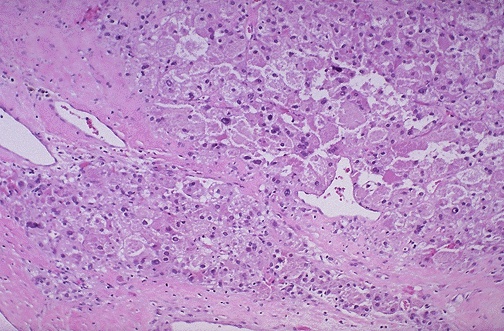

At higher power, the neoplastic cells have pale pink to clear cytoplasm; nuclei show pleomorphism.